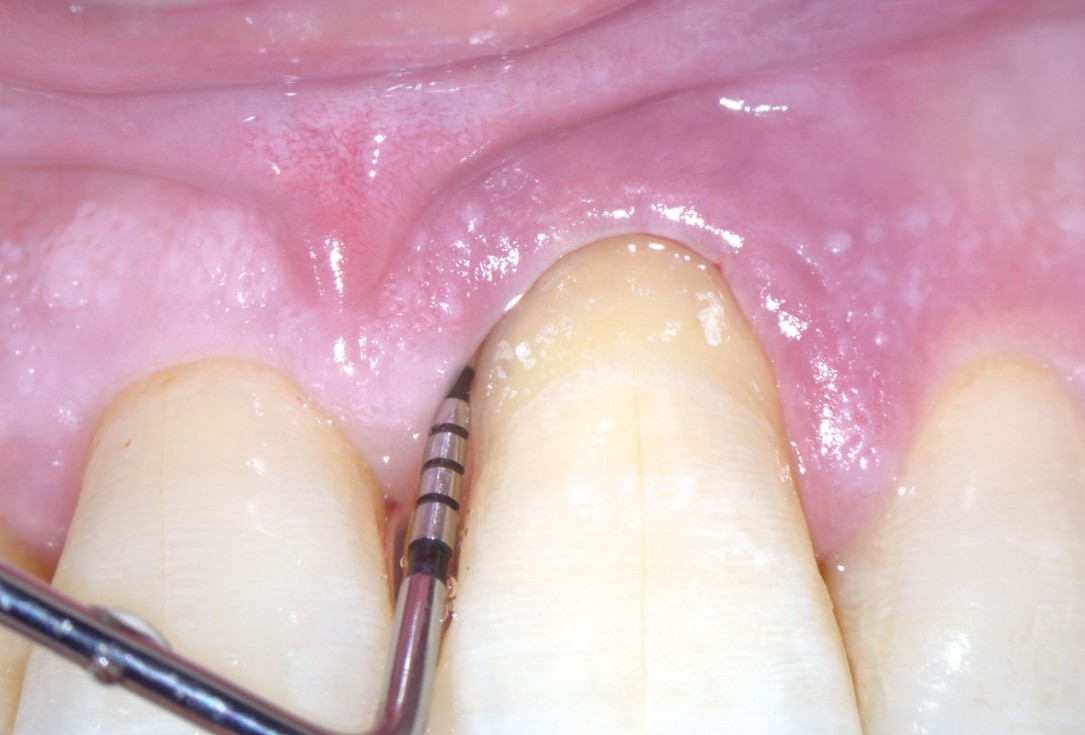

03/11 - Probing depth of 10 mm after non-surgical therapy with a 13 mm clinical attachment level (CAL)Entire papilla preservation technique (EPP) for the regenerative treatment of a severely compromised central incisor - Dr. S. Aslan